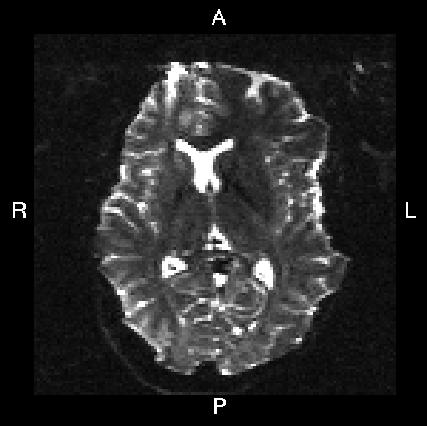

Here is a visual "cheat sheet" for what to put into your --acqp file

| What you see in FSLeyes |

![]() |

|---|---|---|---|---|

| First three columns in --acqp file | 0 1 0 | 0 -1 0 | 1 0 0 | -1 0 0 |